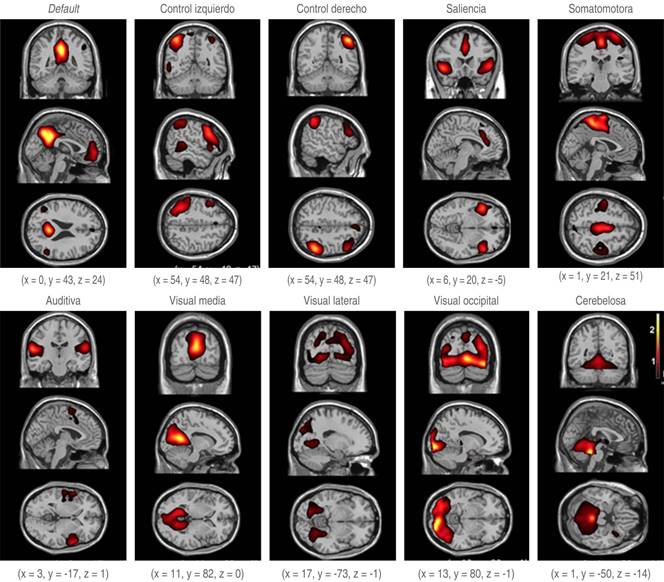

La primera de estas redes fue reconocida y estudiada en 1995 por Biswal y colaboradores. Estos autores describieron la red de default, después de la cual, se fueron descubriendo más redes cerebrales; siete de estas redes se aceptan como fundamentales, aun cuando no hay un consenso universal al respecto ni a su número final. A continuación se describen estas siete redes:

Red de default o frontoparietal medial: incluye las cortezas prefrontal media, posterior del cíngulo y parietal inferior junto con el hipocampo. Tiene como labor la recolección de recuerdos, imaginación, planes a futuro y divagaciones mentales.

Red de control derecha e izquierda: está compuesta por la corteza lateral prefrontal, el lóbulo parietal inferior, gran parte de la circunvolución del cíngulo, la región de la precuña, el tálamo dorsomedial y la cabeza del núcleo caudado. Esta red ejerce el control de la información que fluye a través del cerebro, incluyendo la consciencia y memoria. Está en constante comunicación con otras redes, como son la de default y la de saliencia.

Red de saliencia o adaptación: formada por la región de la ínsula, las cortezas del cíngulo, del parietal inferior y la prefrontal lateral, pero también se incluyen estructuras subcorticales, como la substancia negra, la substancia gris periacueductal, la amígdala, el hipotálamo y el núcleo ventromedial del tálamo. Identifica la información relevante y ajusta rápidamente, momento a momento, las respuestas a los cambios en el medio ambiente y tiene la capacidad de intercambiar la preponderancia transitoria de la red de default y de la red de control, ya que ambas no coexisten habitualmente.

Red somatomotora: compuesta por las regiones anterior y posterior del surco central. Su tarea es el procesamiento tanto motor como sensorial.

Red auditiva: integrada por la circunvolución temporal superior, el área de Heschl (circunvoluciones temporales transversas), la ínsula y la circunvolución postcentral. Percibe, procesa e integra los estímulos de sonido, entregando la información a las redes anteriormente citadas.

Redes visuales: divididas en medial, lateral y occipital. Las áreas que la constituyen se encuentran principalmente en el lóbulo occipital, pero también están las áreas visuales laterales, el cuerpo estriado y el núcleo lateral geniculado del tálamo y la corteza prefrontal.

Red cerebelosa: implicada en el control motor34,35 (Figura 7).